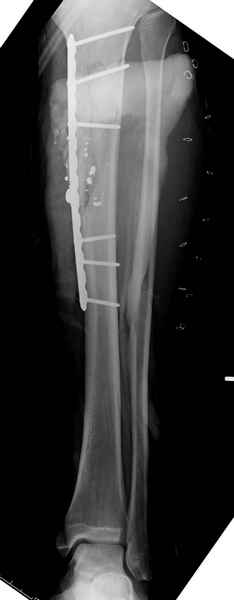

1 неполный перелом большеберцовой кости перкутанная пластина